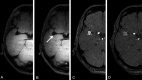

Results: We included 57 patients with 65 unruptured intracranial aneurysms. After a median follow-up of 27 months (interquartile range, 20-31 months), growth (n = 2) or rupture (n = 2) was observed in 4 of 19 aneurysms (21%; 95% CI, 6%-54%) with wall enhancement and in zero of 46 aneurysms (0%; 95% CI, 0%-8%) without enhancement (risk difference, 21%; 95% CI, 3%-39%).